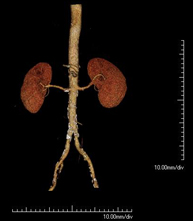

- Abdominal aorta CT angiography

A non-invasive diagnostic test that involves studying the abdominal aorta by obtaining high-definition anatomical images using CT (computed tomography) equipment and iodinated contrast. With the aid of workstations specialised for arterial studies, the image quality supports 2D and 3D reconstructions. It is indicated in patients with vascular disease (atherosclerosis), aortic aneurysms, abdominal pain of possible vascular origin, pre-surgical studies of lesions adjacent to the abdominal aorta as a vascular ‘map’, etc. Information obtained non-invasively is indispensable for patients requiring percutaneous or surgical processing. In patients who only require tracking of vascular lesions, this technique is the non-invasive technique of choice, together with MRI angiography.

- Renal artery CT angiography

A non-invasive diagnostic test that involves studying the renal arteries by obtaining high-definition anatomical images using CT (computed tomography) equipment and iodinated contrast. With the aid of workstations specialised for arterial studies, the image quality supports 2D and 3D reconstructions. This test is recommended, for example, in patients suffering from refractory hypertension that does not respond to processing, in patients with kidney damage in order to obtain a pre-surgical ‘vascular’ map, etc.

- Aortoiliac CT angiography

A non-invasive diagnostic test that involves examining the iliac arteries and abdominal aorta, obtaining high-definition anatomical images using CT (computed tomography) equipment and iodinated contrast dye. With the aid of workstations specialised for arterial studies, the image quality supports 2D and 3D reconstructions. This test is particularly recommended as a pre-surgical study (vascular map) prior to percutaneous or surgical interventions on the abdominal aorta, as a complementary study in patients with lower limb ischaemia, etc.